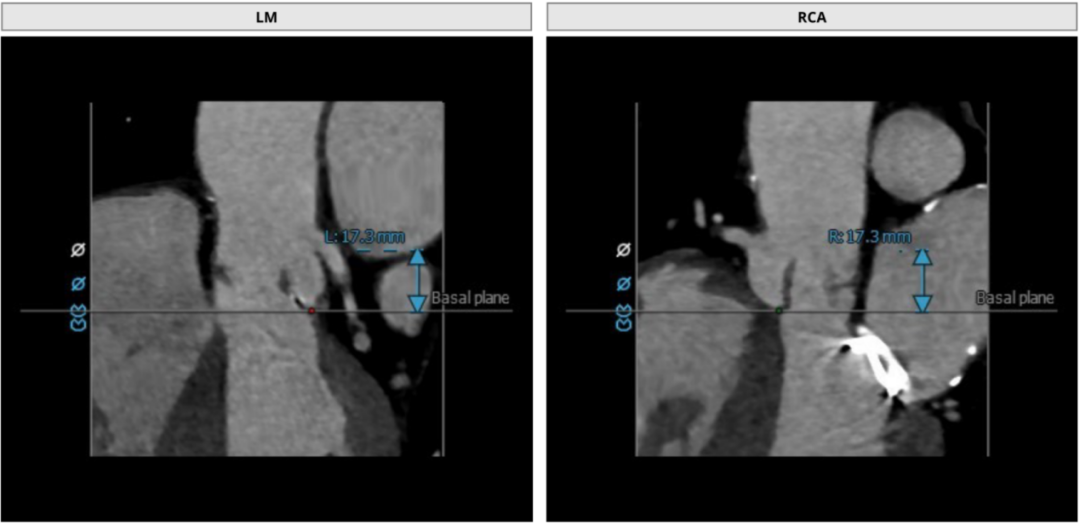

术前CT测量

瓣环:24.4mm;LVOT:22.7mm;

瓦氏窦:32.0*31.4*32.0mm;

升主动脉:32.6mm;左冠高度:17.3mm;

右冠高度:17.3mm;钙化积分:1.1mm³;

瓣环与水平面夹角:34°;

髂外动脉:6.4*8.0mm,6.8*7.9mm。

CT评估

主动脉瓣为三叶瓣,瓣叶肥厚且冗长,CT下可见少量钙化点,窦部结构和冠脉高度尚可,人工金属二尖瓣环,最高处距离主动脉瓣环6.9 mm。大血管走行自然,未见明显迂曲及钙化斑块,下肢血管内径可。